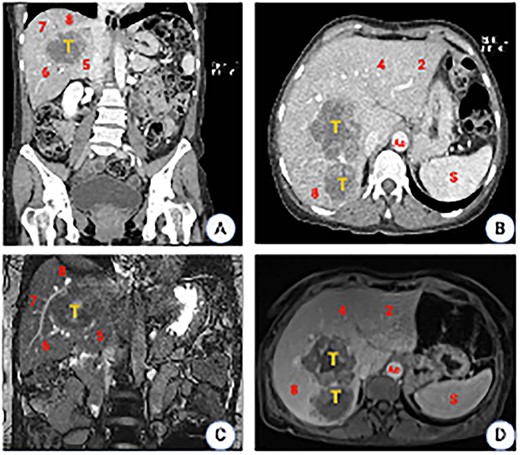

In July 2022, a 49-year-old female, otherwise healthy, presented symptoms of hematochezia and stool caliber changes. A colonoscopy was done, where an exophytic neoplastic lesion was detected on the mucosal surface, measuring around 8 × 3 cm, dark brown, friable and close to obstruction (approximately 70%) at the level of the sigmoid colon, a biopsy of that lesion, pathology reported a moderately differentiated invasive adenocarcinoma originated in the background of a colonic adenoma with high-grade dysplasia. A computed tomography (CT) scan was ordered showing a 7 × 3 cm mass in the sigmoid colon as well as a couple of lesions in the liver in segments 5, 6, 7 and 8, consistent with metastasis. A radical resection of the primary cancer with a left hemicolectomy was with primary anastomosis. After recovering from surgery, the patient was considered for systemic treatment based on eight cycles of oxaliplatin and capecitabine. A new CT scan showed two liver lesions measuring 5 and 6 cm, occupying segments 5, 6, 7, and 8, in addition to at least two other smaller lesions in segments 6 and 7, with no abnormal enhancement under contrast. A liver magnetic resonance imaging (MRI) (June 2023) showed the same lesions corresponding to metastatic deposits, conditioning dilation of the intrahepatic bile duct mainly on its right posterior branch (Fig. 1).

CT scan images. (A) Coronal plane showing the tumor location involving segments 5, 6, 7 and 8. (B) Axial plane showing the relation to the inferior vena cava (IVC). (C) MRI showing a liver mass with peripheral and heterogeneous central enhancement. (D) Axial MRI (T1phase). Ao, aorta; S, spleen.